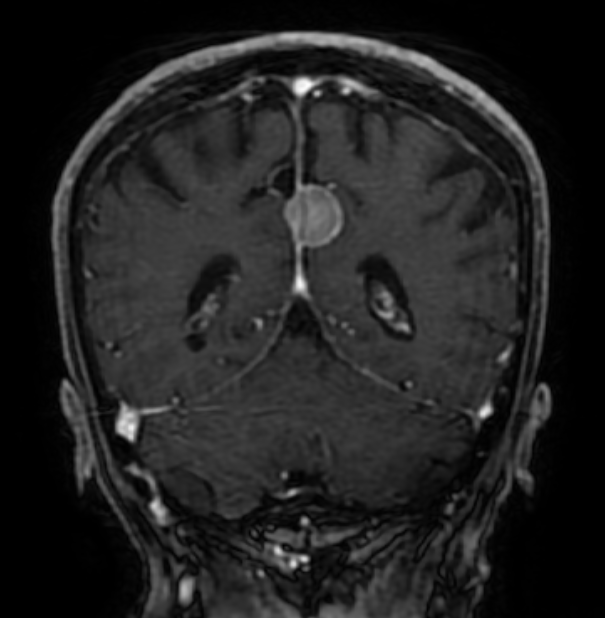

The answer is 2) the lesion is extra-axial. Take a look at the brain MRI’s below to prove it to yourself.

The answer is 1) these lesions often contain small bits of calcium, called psammoma bodies. You have probably guessed by now that General Wood had a meningioma – a brain tumor that is usually benign, although they can cause significant symptoms depending on their location and degree of mass effect. Meningioma’s rarely recur after surgical resection, although unfortunately for General Wood, his did.

Meningiomas should be broad based to the dura, as is the example shown here, which grows out of the falx cerebri. Most are sporadic, but exposure to ionizing radiation is a risk factor for late life meningiomas.